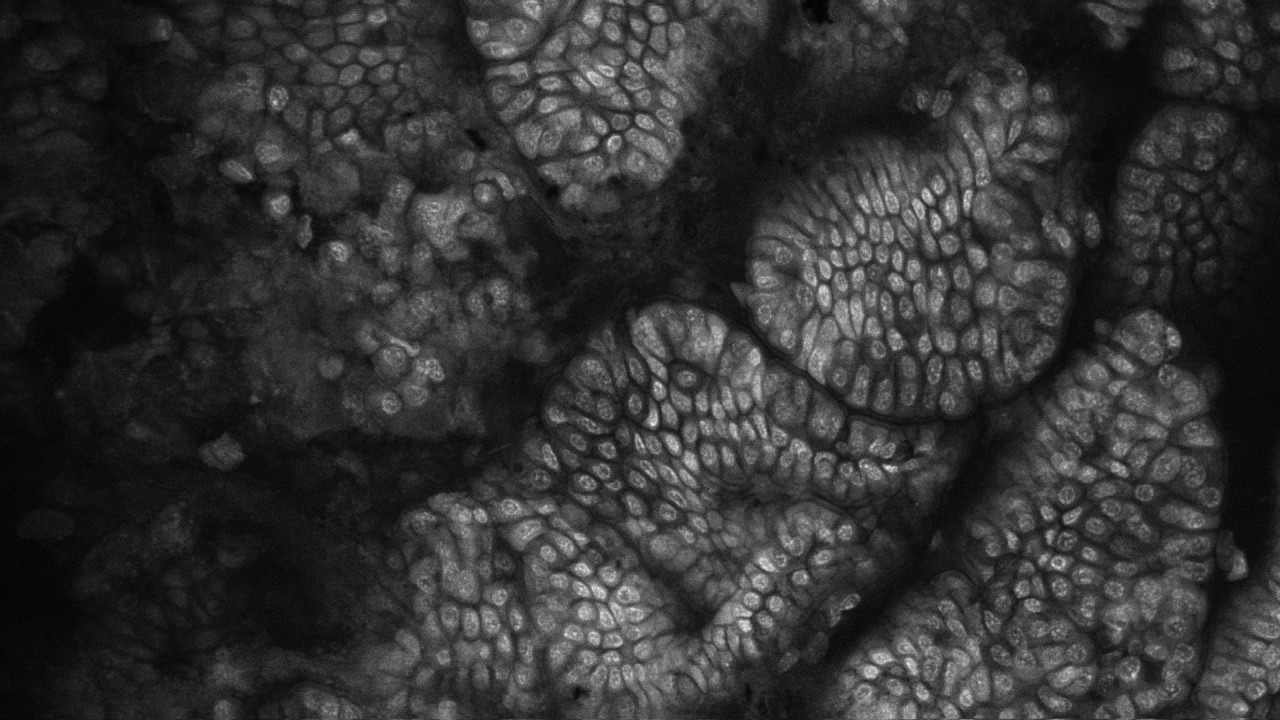

Advancing Veterinary Medicine: The Power of Precision Imaging

Dog small intestine

17-Sep-2024 by Leah Sneddon